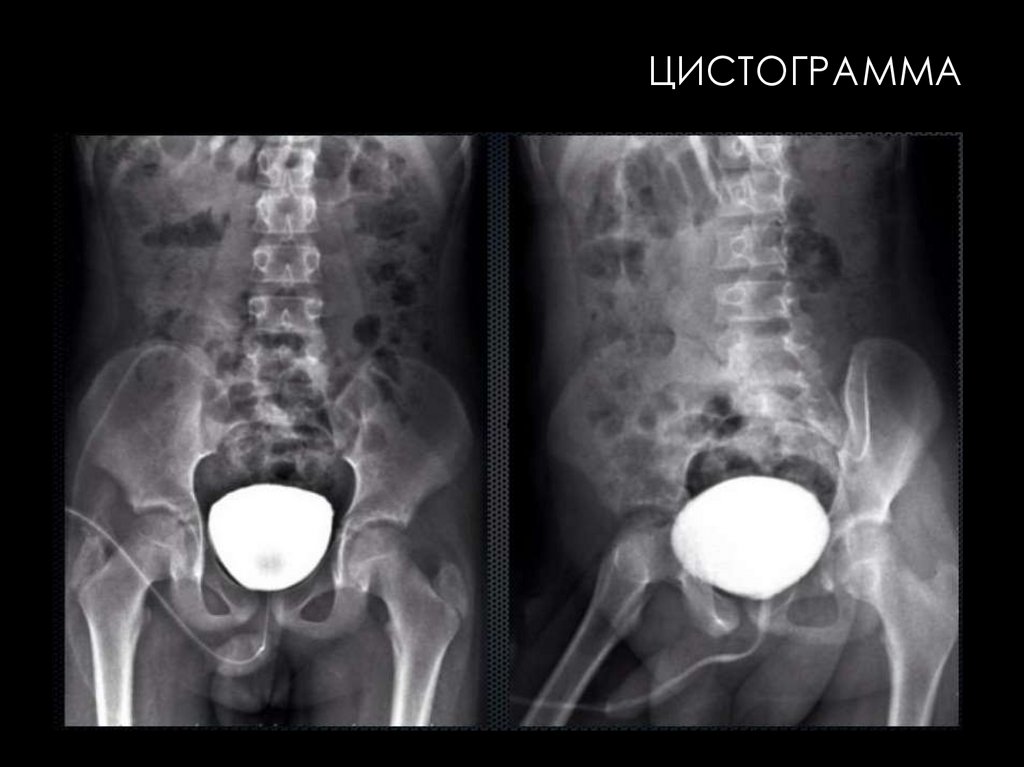

ЦИСТОГРАММА

ЦИСТОГРАФИЯ

• Цистография - это инструментальный метод

исследований мочевого пузыря, который

заключается в рентгенологическом снимке

после заполнения органа водорастворимым

контрастом. В зависимости от пути введения

контрастного вещества, цистография бывает

восходящей или нисходящей.